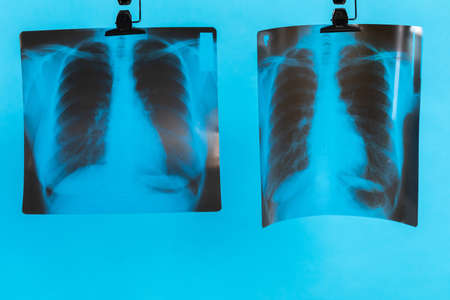

Tuberculosis treatment concept. X-ray of the lungs, with pathology, phonendoscope with pills on the table. Lung disease. Pneumonia. Medical flatley, pills and x-ray image, with phonendoscope, on a blue background. The treatment of bronchitis. Chemotherapy